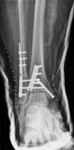

Visão lateral de uma fratura trimaleolar após a fixação

Do acervo de B. Petrisor, MD; usado com permissão